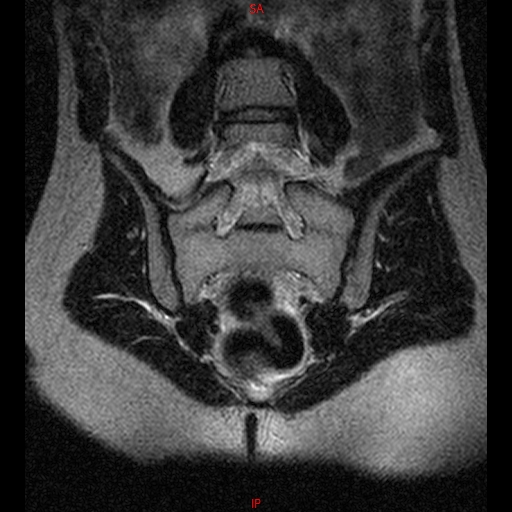

• RESONANCIA NORMAL SACROILIACAS COR T2

• RESONANCIA NORMAL SACROILIACAS  AXIAL T1

• RESONANCIA NORMAL CADERAS T2 CORONAL

• RESONANCIA NORMAL CADERAS T1 CORONAL